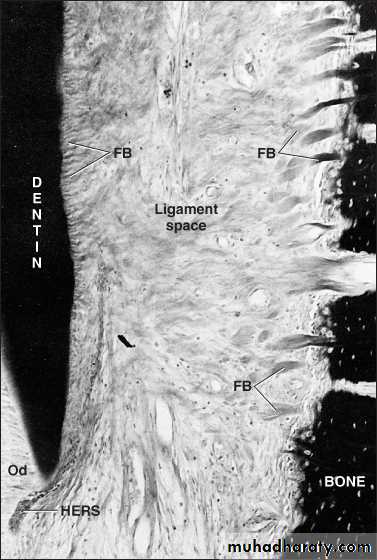

The periodontal ligament is a fibrous C.T ligament located between the alveolar bone proper and cementum. This ligament covers the root of the tooth and connects with the tissue of the gingiva. The p.d.l. occupies the periodontal space and is composed of cell and intercellular substance. It has a thickness of 0.15-0.38 mm, it is thinnest in the mid root zone, and decrease slightly in thickness with aging.

The formation of P.d.l. occurs after the cells of hertwig’s epithelial root sheath have separated, forming the strands known as (the epithelial rests of malassez). This separation permits the cells of the dental follicle to migrate to the exernal surface of the newly formed root dentin. these cells show high degree of mitotic activity, thus differentiating into different types of cells which give rise to cells of periodontal ligament namely: Cementoblast deposit cementum on the surface of dentin, Osteoblast of the developing alveolar bone, and Fibroblast to synthesize the fibers and ground substance of periodontal ligament, The fibers of p.d.l. become embedded in newly developed cementum and alveolar bone, and as the tooth erupt. Other cells of the dental follicle differentiate into fibroblasts, which synthesize the fibers and ground substance of p.d.l

Collagen macromolecules are arranged to form fibrils, these fibrils are packed to form bundles or fibers that oriented relative to periodontal space and these are termed principal fibers.

The principal fibers run a wavy course from cementum to bone.

Microscopical examination showed that fibers arising from cementum and bone are joined in the mid-region of periodontal space, giving rise to a zone of distinct appearance, called intermediate plexus, this region provides a site where rapid remodeling of fibers occurs, allowing adjustments in the ligament to be made to accommodate small movements of tooth.Intercellular tissue